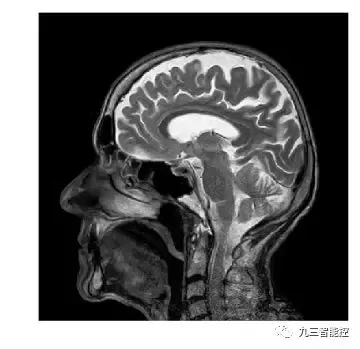

(5)大脑核磁共振图像(侧面)

原始图像